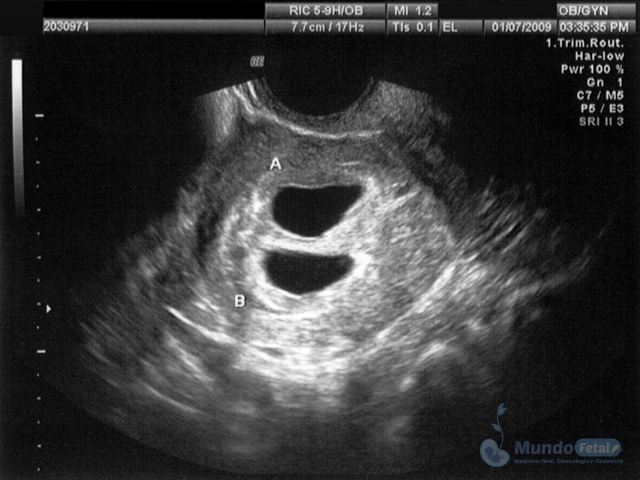

Ultrasonido Embarazo Múltiple

Es esencial detectarlo desde el primer trimestre (especialmente 11-13.6 semanas de gestación) con la intención de conocer el número de bebes, cuántas placentas y bolsas amnióticas, ya que el seguimiento de estos es distinto, esto por los riesgos que conllevan de presentar alguna alteración propia de estos embarazos, indicativos de una vigilancia estrecha y estudios complementarios, durante toda la gestación.

• Descartar o confirmar oportunamente riesgos y anomalías, sugerentes de vigilancia y estudios complementarios.